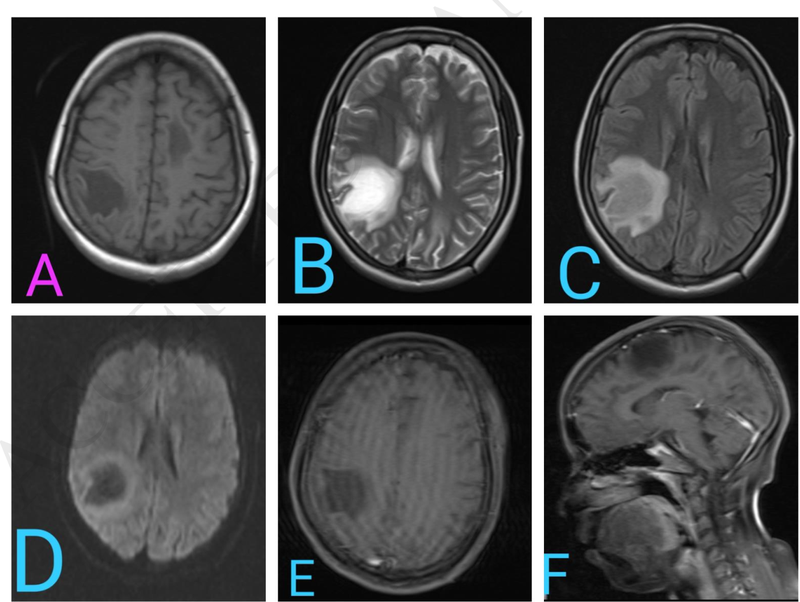

Những người mắc hội chứng Cotard được cho thấy có xu hướng xuất hiện những thay đổi trong não, do đó có thể thần kinh đóng một vai trò tiềm ẩn trong sự phát triển của hội chứng này.

Nguyên nhân gây hội chứng Cotard vẫn chưa được xác định rõ ràng. Tuy nhiên, nghiên cứu cho thấy hội chứng này có thể liên quan đến các bệnh lý tâm thần kinh như sa sút trí tuệ, bệnh não do virus hoặc nhiễm độc, động kinh, đau đầu migraine, đa xơ cứng, bệnh parkinson, đột quỵ và tụ máu dưới màng cứng.